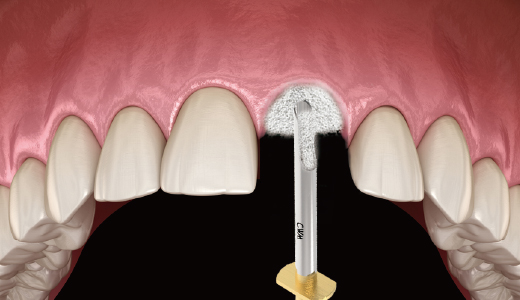

임플란트에 CowellBMP 코팅 시 : CowellBMP 용액을 원형 홈에 3~4방울 떨어트려서 임플란트에 코팅

1. Bone Carrier의 원형 홈에 먼저 rhBMP-2 용액을 주사

-

2. Hand-piece를 이용하여 원형 홈에 Fixture를 천천히 회전